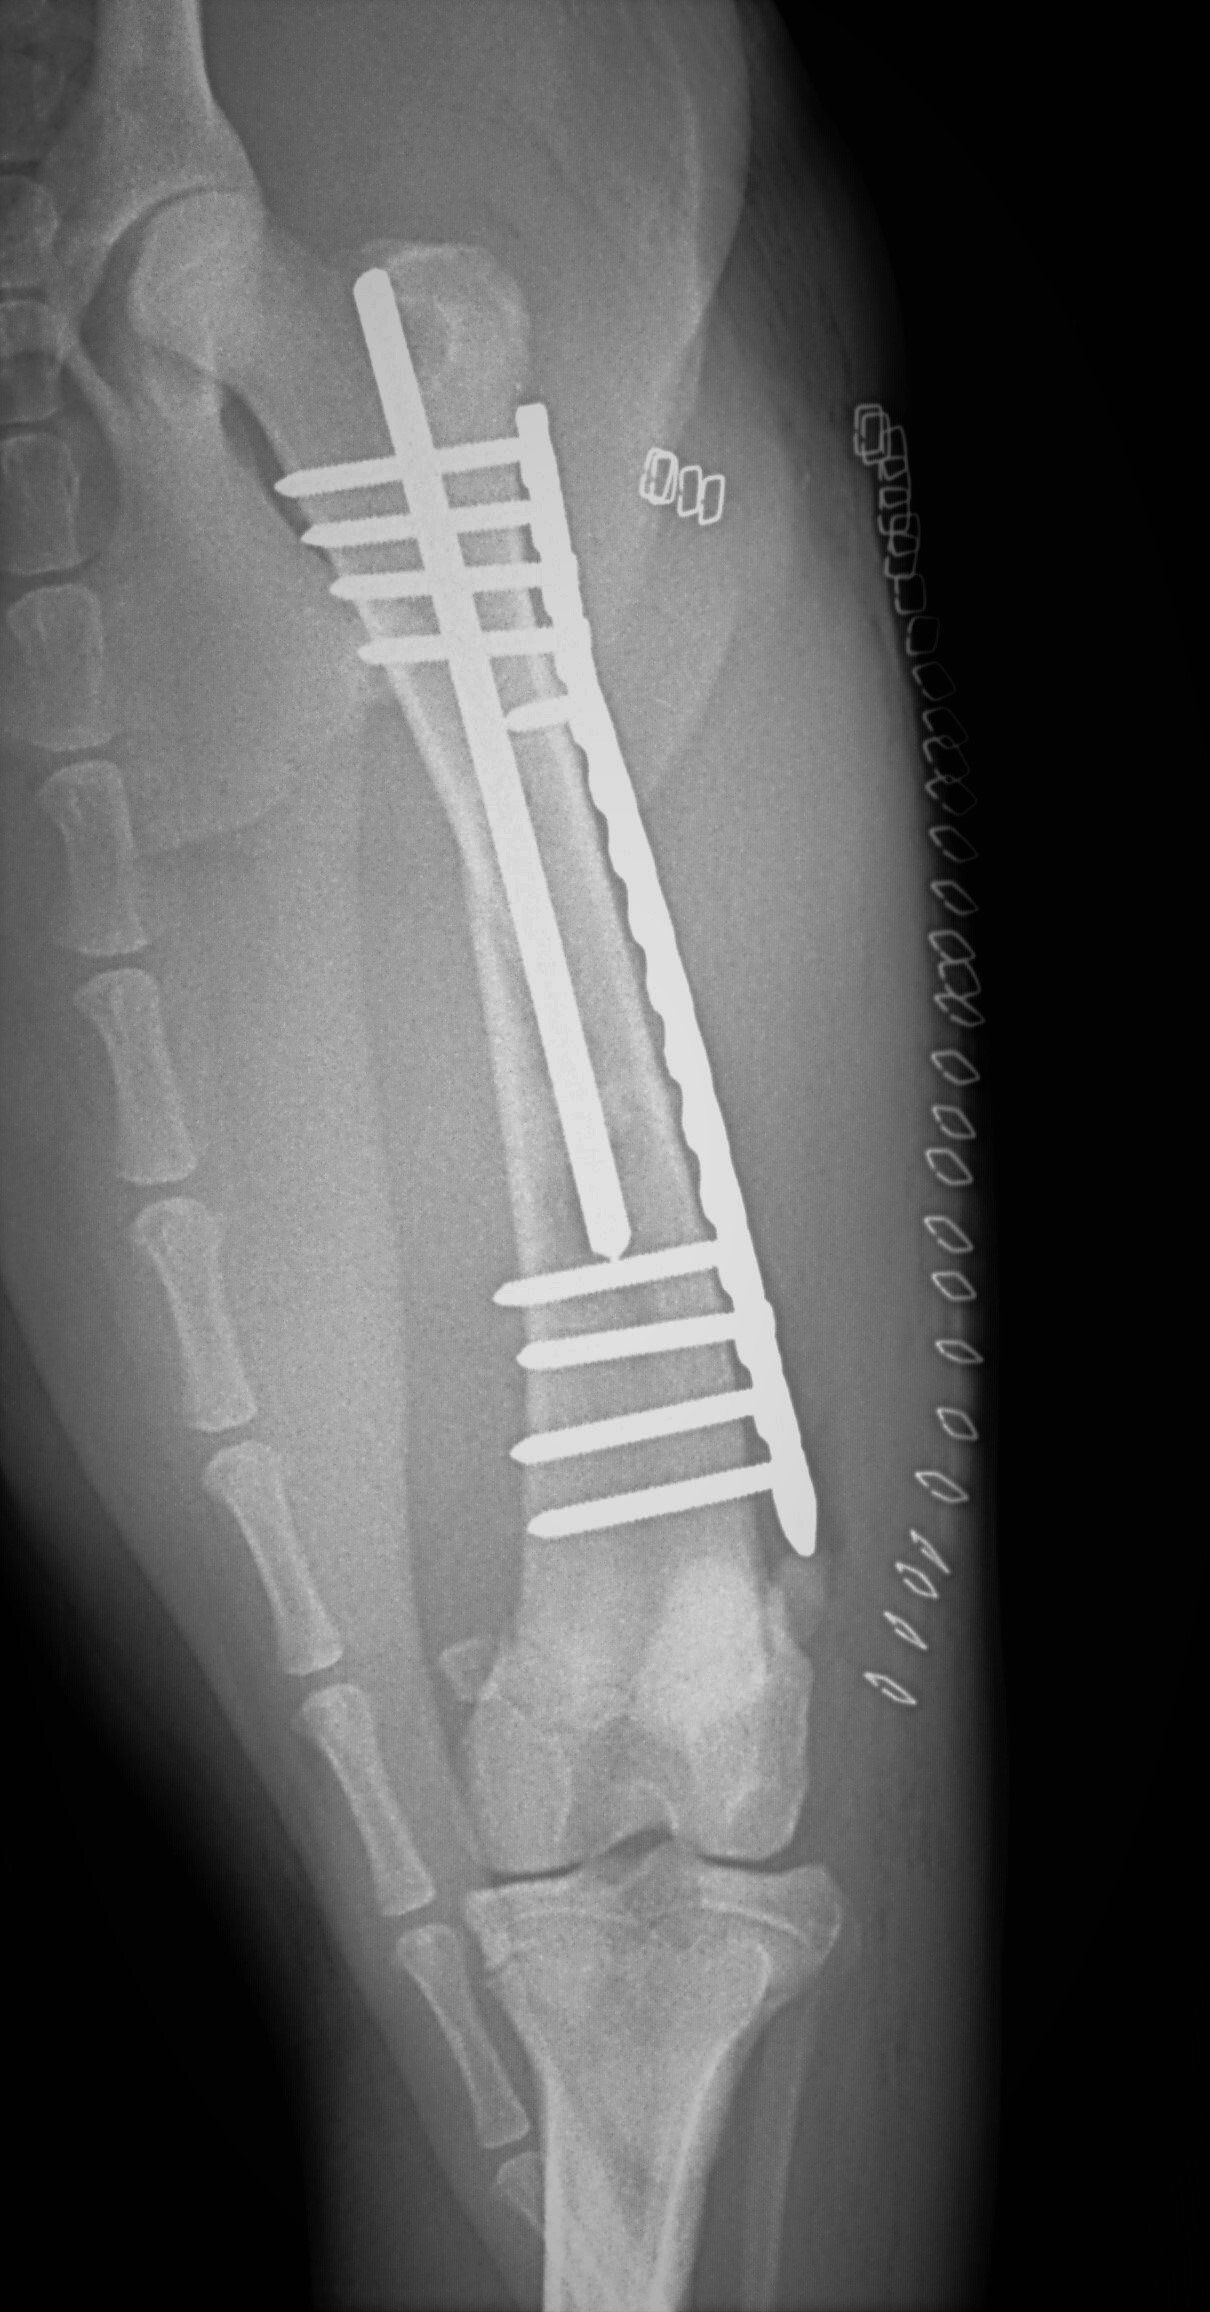

Leg fractures are one of the most common orthopedic problems presented at our clinic and usually result from a traumatic mishap. They can be treated in a variety of ways depending on the location and type of fracture. We can apply a cast to treat certain fractures; however, many fractures will require surgical intervention:

- “Pinning” stabilizes the fracture by inserting a long stainless steel rod into the middle of the bone across the fractured area.

- “Plating” involves attaching a flat stainless steel plate to the bone using screws on either side of the fracture.

Below are x-rays of just a few orthopedic surgeries before and after that Dr. Gose has performed.